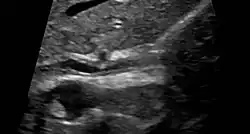

Ultrasound of sclerosing cholangitis in the common bile duct

PSC is generally diagnosed on the basis of having at least two of three clinical criteria after secondary causes of sclerosing cholangitis have been ruled out:

• serum alkaline phosphatase (ALP) > 1.5x the upper limit of normal for longer than 6 months

• cholangiography demonstrating biliary strictures or irregularity consistent with PSC

• liver biopsy consistent with PSC (if available)

Historically, a cholangiogram would be obtained via endoscopic retrograde cholangiopancreatography (ERCP), which typically reveals "beading" (alternating strictures and dilation) of the bile ducts inside and/or outside the liver. Currently, the preferred option for diagnostic cholangiography, given its noninvasive yet highly accurate nature, is magnetic resonance cholangiopancreatography (MRCP), a magnetic resonance imaging technique. MRCP has unique strengths, including high spatial resolution, and can even be used to visualize the biliary tract of small animal models of PSC.[22]